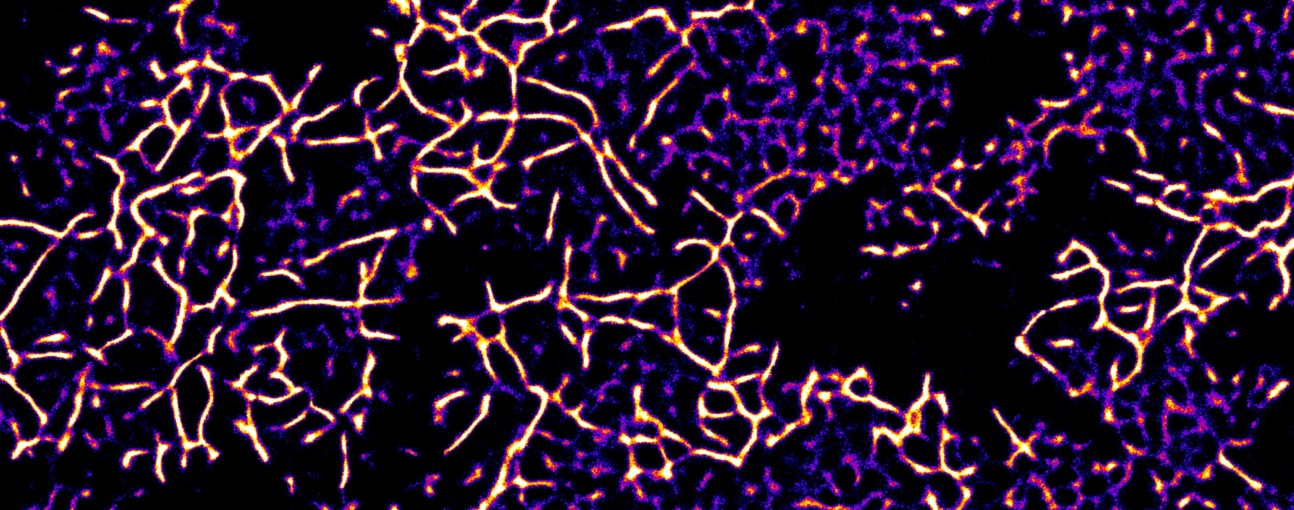

Alpha-synuclein Aggregates - Michael Morten (Research Associate: Ye lab)

"Super-resolved alpha-synuclein aggregates deposited on a glass slide"